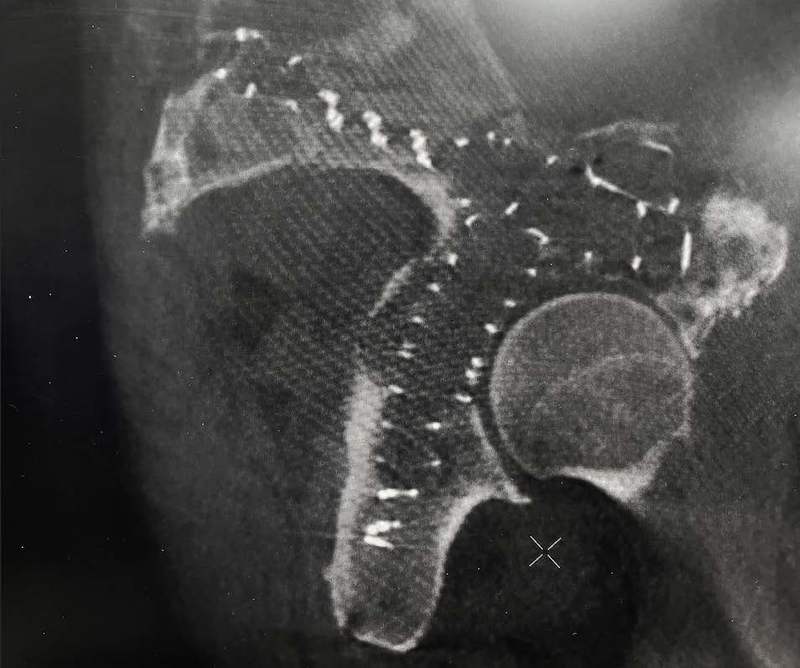

The 63-year-old patient presented with a pathologic acetabulum/hemi-pelvic fracture, and osteolysis with uncontained defect from metastatic lung cancer and additional co-morbidities. The patient has been treated with radiation for metastatic bone disease of the pelvis, and was bed ridden living in a skilled nursing facility due to severe pain and dysfunction resulting from his pathologic pelvis fractures. The patient was brought to surgery and IlluminOss implants were inserted percutaneously through the posterior column, anterior column and LC2 to provide fill and stability for the uncontained osteolytic defect. The implants were filled with a photodynamic liquid monomer and cured with visible blue light. At post-op day 1, the patient was weight bearing as tolerated using a walker. The patient was discharged back to the SNF on post operative day 1 and then from the SNF to home at 2 weeks post procedure. At 6 weeks follow up, patient uses the walker in the community and ambulates unassisted intermittently at home.